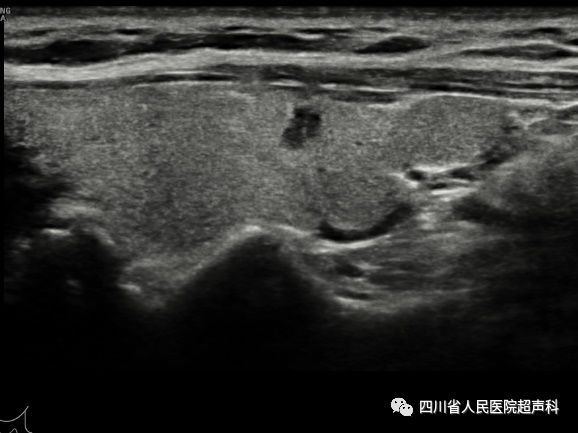

图2 女,61岁,右侧甲状腺低回声结节7mmx6mm,TI-RADS 4a类